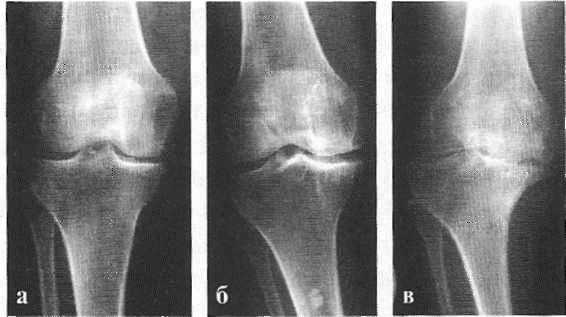

В подавляющем большинстве случаев достаточно осмотра и рентгенограммы коленного сустава в двух проекциях (прямой и боковой). [2] [19] Клинические данные и снимки позволяют определить стадию заболевания.

На ранних стадиях заболевания, при незначительных изменениях в костной ткани, рентгенологическое обследование не настолько ценно. [5] [8] На этом этапе гонартроз возможно диагностировать благодаря артроскопии. [5] [8] Точность метода очень высока, останавливать может только его инвазивный характер и цена.

Инструментальные исследования: рентгенологическое исследование суставов - для подтверждения диагноза ОА, стадии и оценки прогрессирования дегенеративных изменений в суставах; стадию заболевания определяют преимущественно по классификации KellgrenLawrence. Новые инструментальные методы (спектроскопия ядерно- магнитного резонанса, КТ, остеоцинтиграфия, УЗИ суставов) применяют для изучения характера поражения всех составляющих сустава, но не для оценки эффективности лечения.

Рентгенологическое исследование помогает поставить диагноз, но не дает прогнозов по дальнейшему развитию симптомов заболевания. Рентгенограммы могут показать обширные изменения, но это не всегда означает в клинике сильную боль или нетрудоспособность пациента.